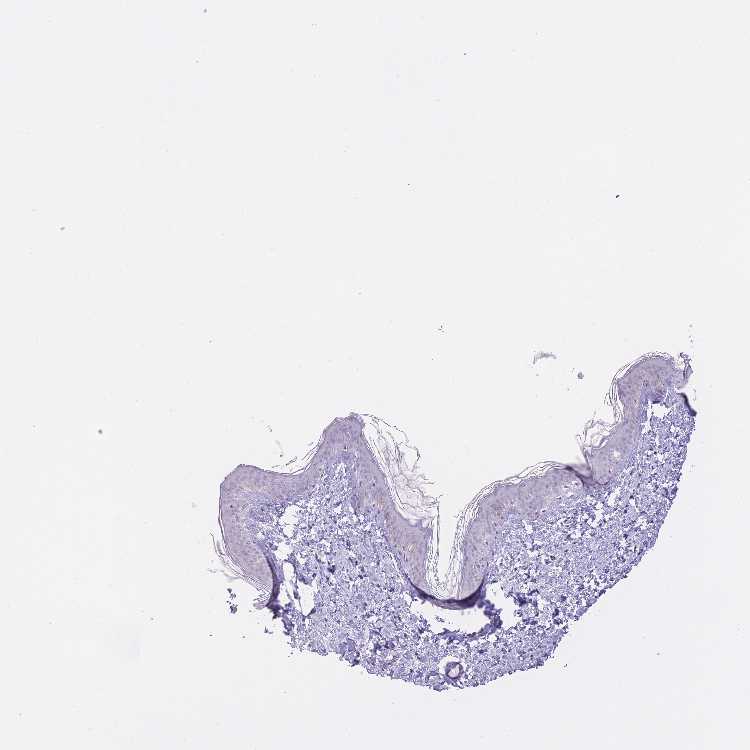

SKIN 1 - Antibody stainingi

Antibody staining in the annotated cell types in the current human tissue is reported as not detected, low, medium, or high, based on conventional immunohistochemistry profiling in selected tissues. This score is based on the combination of the staining intensity and fraction of stained cells.

Each image is clickable and will lead to virtual microscopy that enables deeper exploration of all samples and also displays staining intensity scores, fraction scores and subcellular localization as well as patient and tissue information for each sample.

Antibody HPA048149

Langerhans Not detected

Fibroblasts Not detected

Keratinocytes Not detected

Melanocytes Not detected